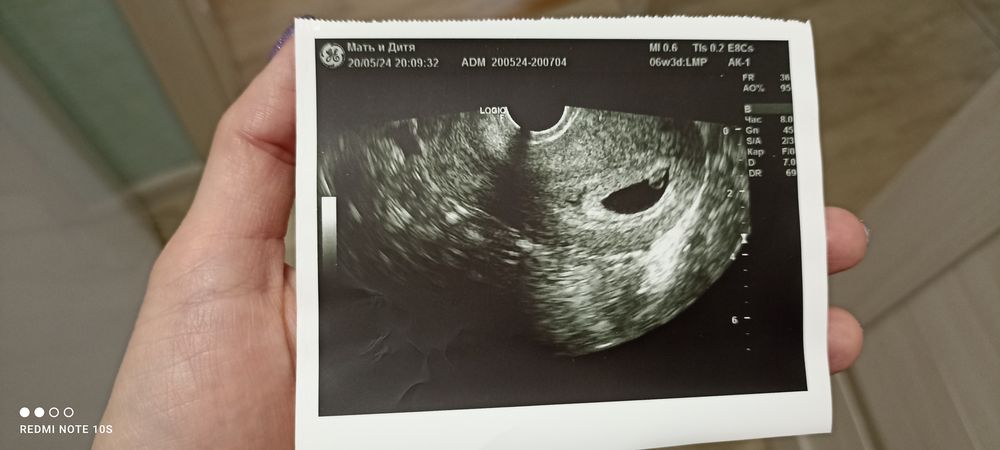

Спасибо за эти слова! За эти мысли. Мы на пути планирования уже много-много лет. Была и внематочная и выкидыши и потеря дочки в родах. Спустя 5 лет, именно 18 мая (в день потери) я делаю совсем случайно тест (не планировали, готовимся к эко) И вижу//. Тихонечко молимся и верим 🙏🏻 И будто так и должно было быть, именно сейчас, именно в этом возрасте

УЗИ 37 дпп Перимембранозный ДМЖП